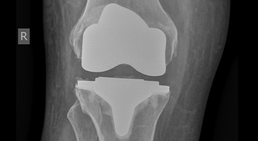

Knieprothese (Kniegelenkersatz)

Ein schmerzendes Knie kann auf eine Kniegelenkarthrose hinweisen. Dabei handelt es sich um eine verschleißbedingte Erkrankung des Kniegelenks, bei der der...